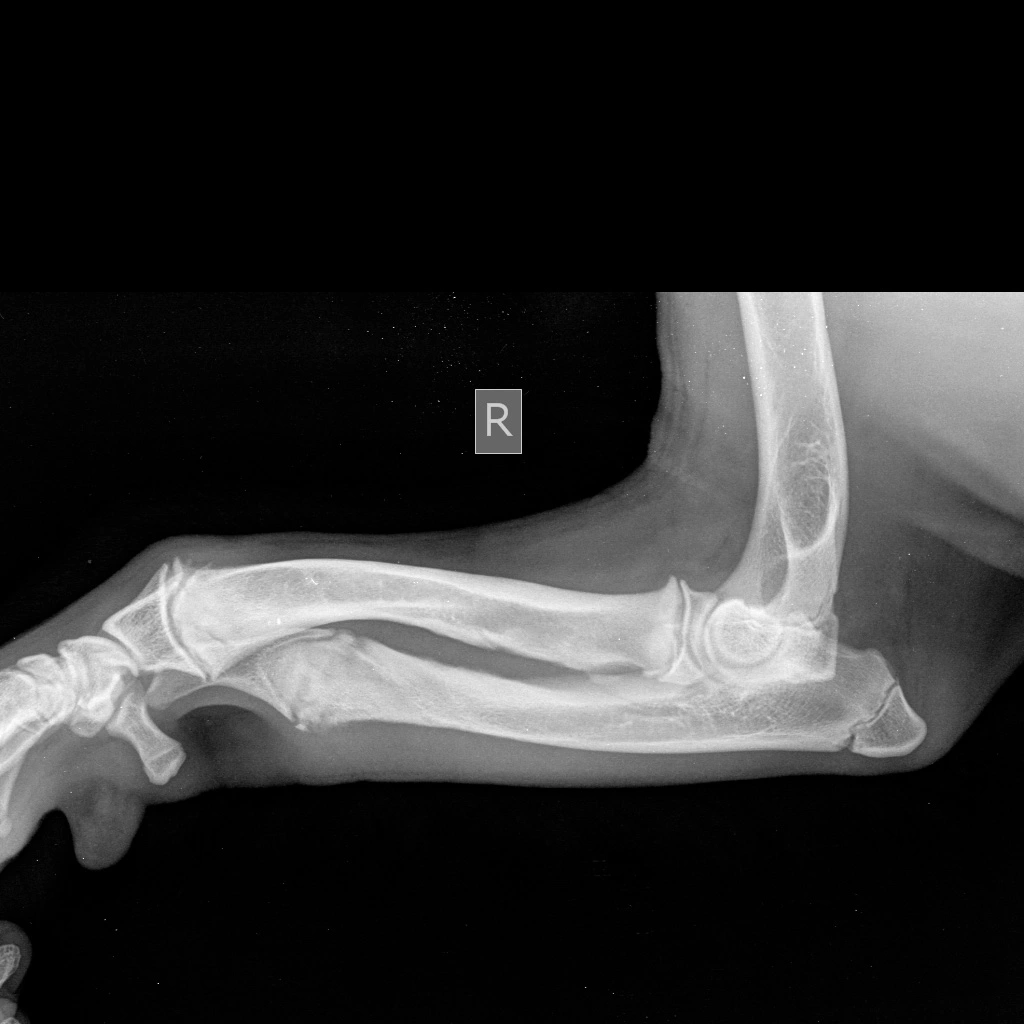

Предплечье состоит из двух костей (лучевой и локтевой), в норме они развиваются синхронно. При заболевании отмечается раннее закрытие зоны роста локтевой кости, что останавливает ее рост, в то время как лучевая кость продолжает увеличиваться в длину. Дальнейшему росту кости препятствуют локтевые и запястные суставы, что вызывает избыточное давление на них и искривление самой кости. Патологическое давление на сустав вызывает развитие дегенеративного изменения хряща (артроза, артрита, остеоартрита).

Основными клиническим признаками является нарастающая хромота и искривление лап в области запястья (так называемый «размет лап», а также припухлость в области локтевого сустава и его малоподвижность).

Диагноз ставится на основании анамнеза, ортопедического осмотра и инструментальных методов диагностики, таких как рентгенография и компьютерная томография (КТ), при которых врач может оценить стадию заболевания и выбрать подходящую тактику лечения.